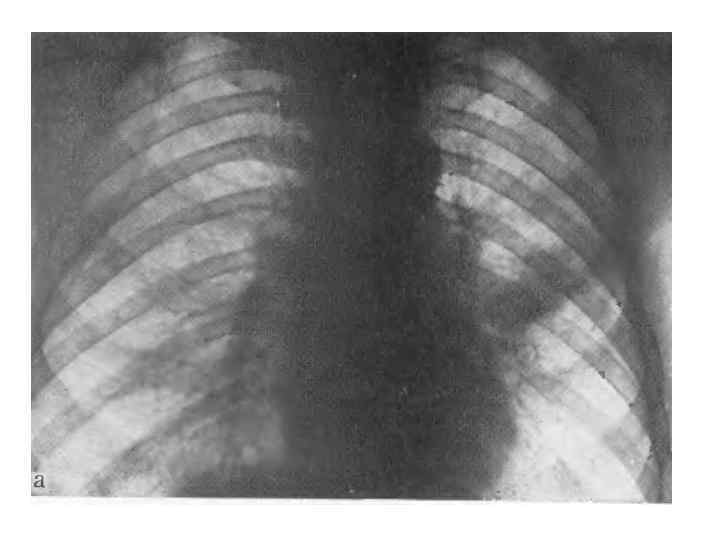

Рис. 235. Ателектаз нерхней доли. а — прямая рентгенограмма; 6 — боковпя'ренттенограмма. Смещение дачи вверх и кпереди.